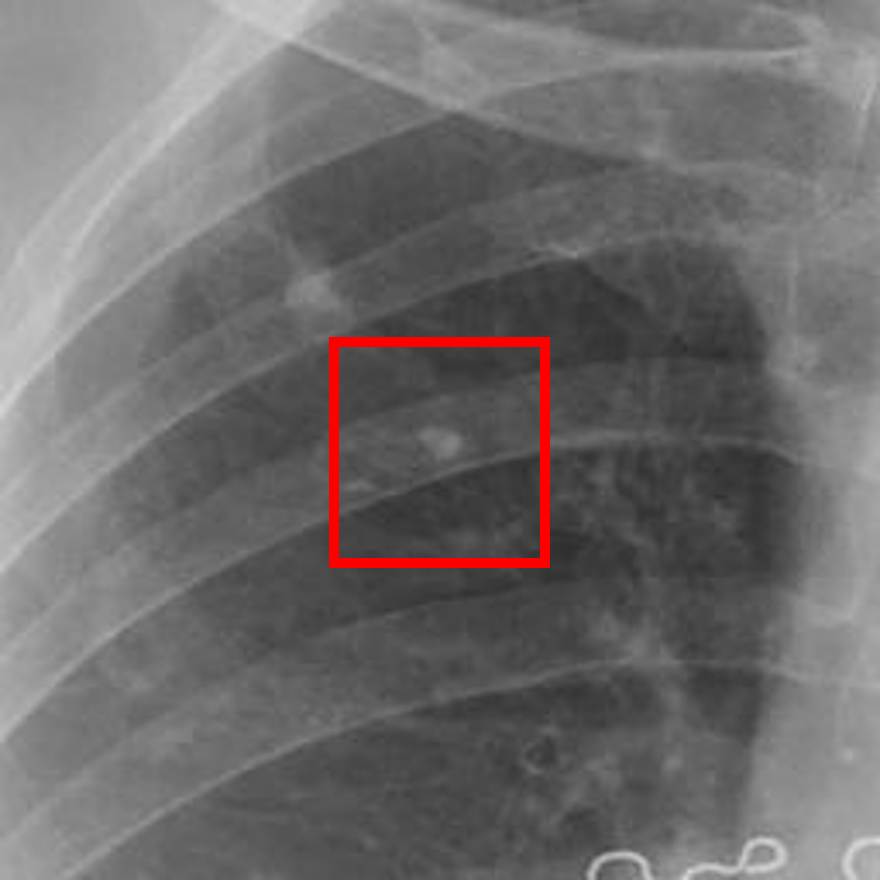

Refer to caption

(a) Healthy(1)

(b) NODE21

(c) Healthy(2)

(d) VinDr-CXR

Figure 5: Grad-CAM-based saliency maps illustrating model interpretability across datasets. Top row: Examples from NODE21 showing baseline (a) and curriculum-trained (b) models. Bottom row: Examples from VinDr-CXR demonstrating consistent attention patterns (c, d).

Grad-CAM visualizations showed that curriculum-trained models consistently focused on anatomically meaningful lung regions near nodules (Figure 5b), while baseline models activated broader, clinically irrelevant regions (Figure 5a). Similar attention patterns were observed across NODE21 and VinDr-CXR examples (Figure 5c,d), supporting interpretability and robustness.